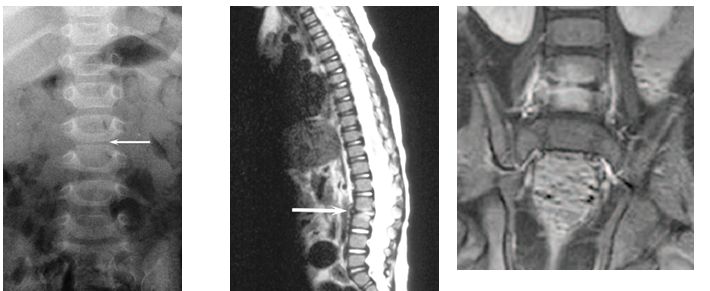

Rx toracolumbar muestra disminución de la altura del disco entre L5-S1 y perdida de la claridad. RM confirma los hallazgos de la Rx.

El diagnóstico más probable es discitis L5-S1. Las imágenes por resonancia magnética de la columna, muestra abombamiento tanto anterior y posterior del disco L5-S1, con  erosión de los bordes anteriores, tanto de las vértebras L5 y S1. Existe también evidencia de edema dentro de los cuerpos vertebrales. Las apariciones radiológicas tienen más probabilidades de ser compatible con una discitis suave.

Resonancia Magnética de columna al ingreso.